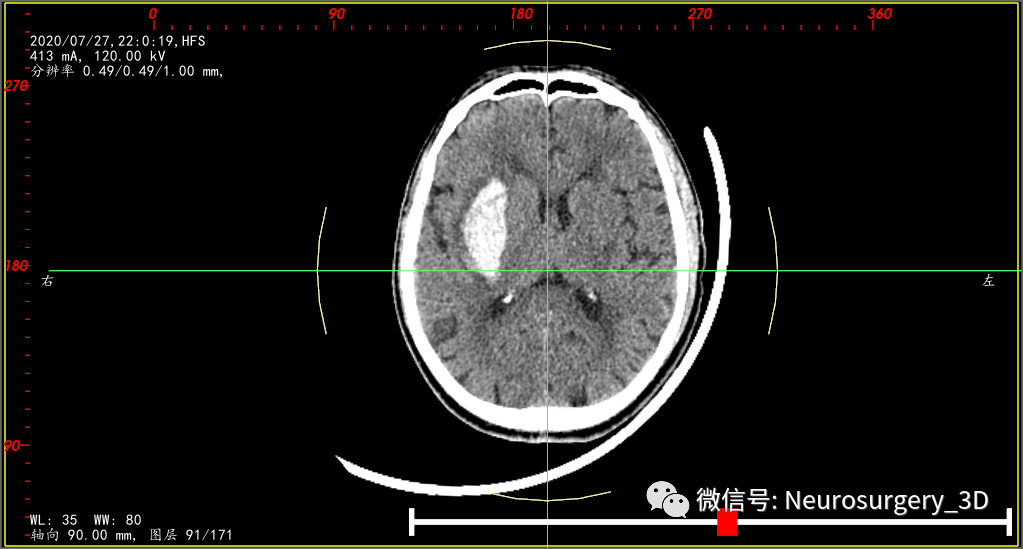

为了料敌于先,排除活动性出血,入院后10小时给予复查颅脑CT,如下:

再次三维重建仍是17ml左右

复查后反复阅片,真的与第一次CT没有明显差别,宁愿做个事后诸葛亮,也没有发现这次CT有什么异常。